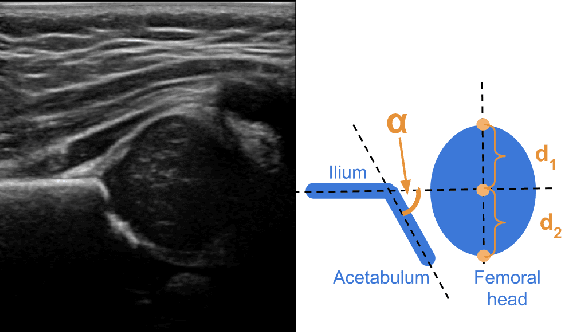

Abstract:Deep learning approaches often require huge datasets to achieve good generalization. This complicates its use in tasks like image-based medical diagnosis, where the small training datasets are usually insufficient to learn appropriate data representations. For such sensitive tasks it is also important to provide the confidence in the predictions. Here, we propose a way to learn and use probabilistic labels to train accurate and calibrated deep networks from relatively small datasets. We observe gains of up to 22% in the accuracy of models trained with these labels, as compared with traditional approaches, in three classification tasks: diagnosis of hip dysplasia, fatty liver, and glaucoma. The outputs of models trained with probabilistic labels are calibrated, allowing the interpretation of its predictions as proper probabilities. We anticipate this approach will apply to other tasks where few training instances are available and expert knowledge can be encoded as probabilities.